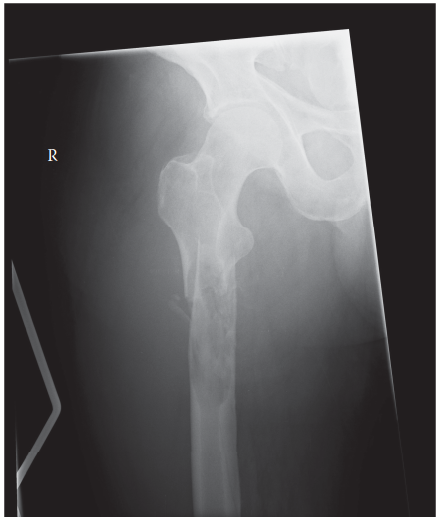

Can you describe the radiograph? This is an AP radiograph of the right hip. There is a pathological fracture …

Advanced osteoarthritis bilaterally. Osteonecrosis and complete obliteration of the joint space on both sides…